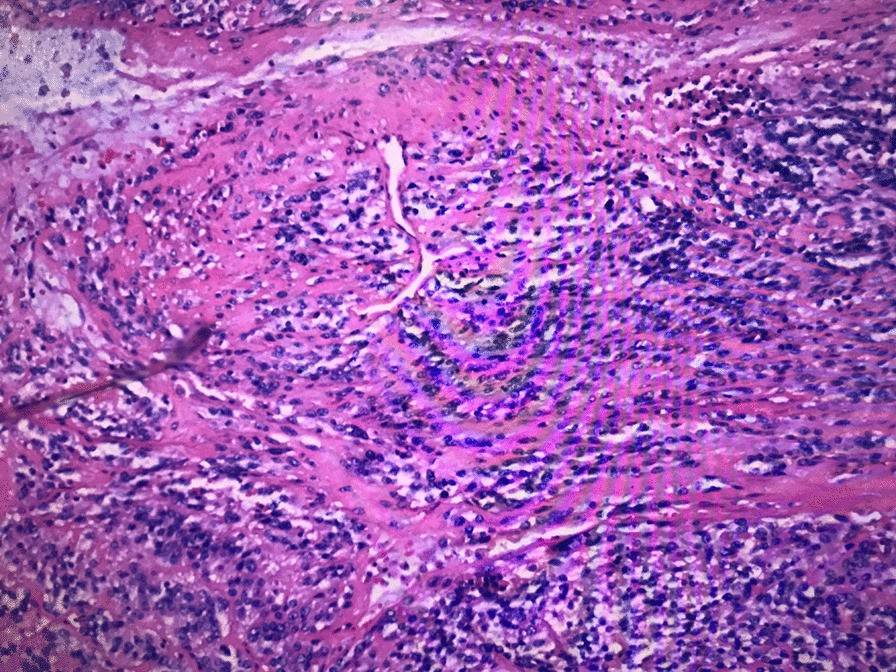

Fibrosarcoma of corpus cavernosum (HE, 100X)